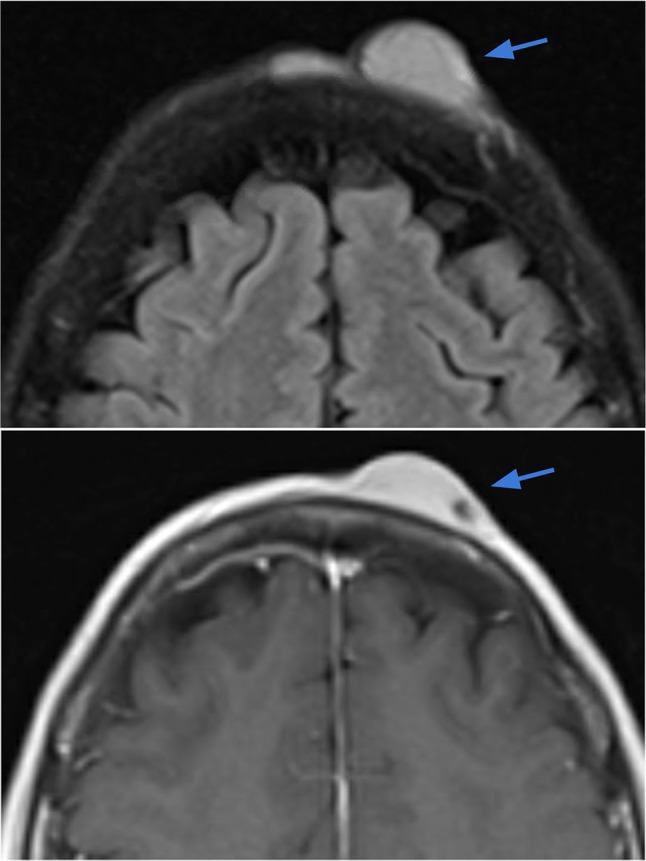

Case 7.

Dermatofibrosarcoma protuberans (DFSP) of the scalp. Axial T2-weighted (right image) and T1-weighted contrast-enhanced (left image) demonstrate a 2.6 × 0.8 cm circumscribed lentiform lesion with T2 hyperintensity and avid contrast enhancement within the left frontal scalp, extending up to the skin surface. The underlying periosteum along the outer table of the skull appears intact